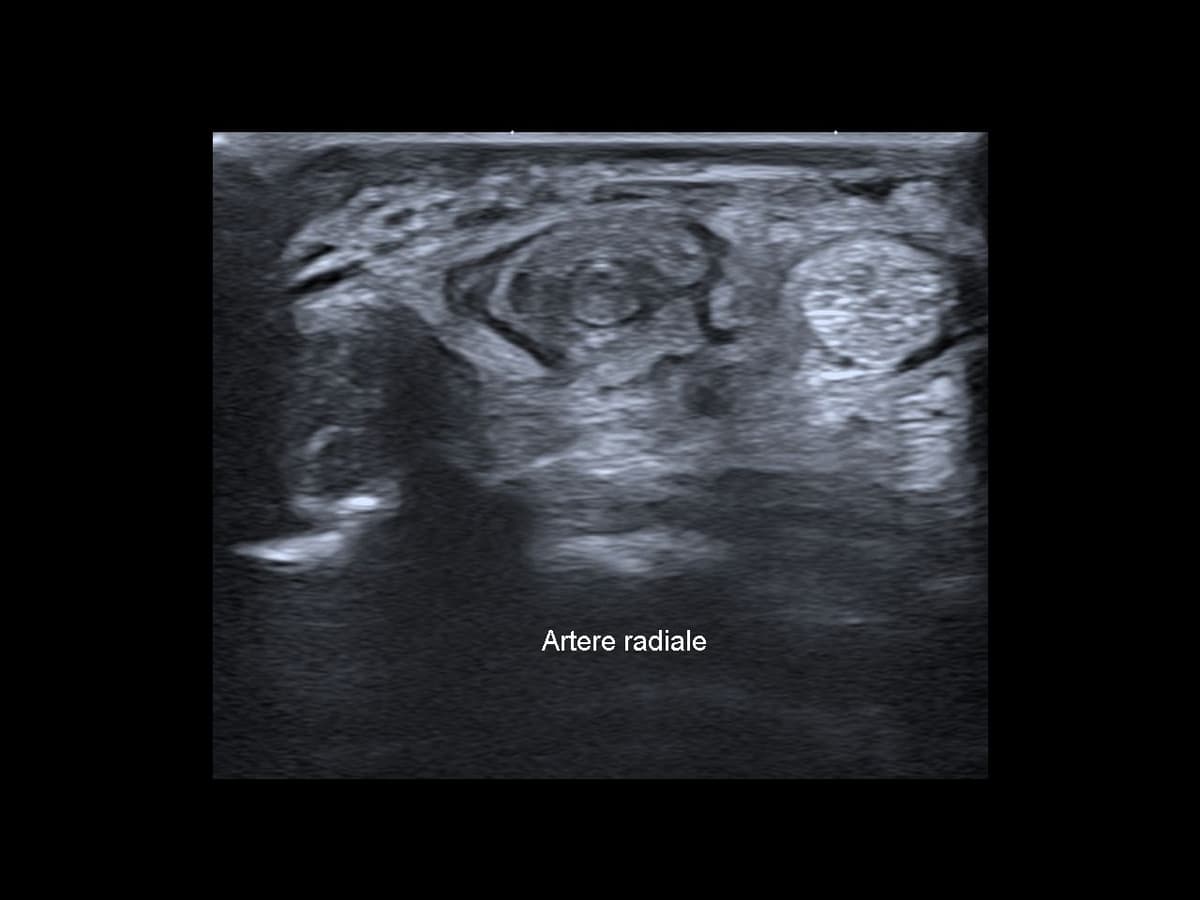

Thrombose de l'artère radiale

Pathologie vasculaire rare caractérisée par la formation d’un thrombus dans l’artère radiale sans antécédent de traumatisme.

US